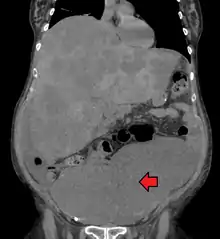

Colon cancer with extensive metastases to the liver

Colorectal cancer diagnosis is performed by sampling of areas of the colon suspicious for possible tumor development, typically during colonoscopy or sigmoidoscopy, depending on the location of the lesion.[18] It is confirmed by microscopical examination of a tissue sample.

Medical imaging

A colorectal cancer is sometimes initially discovered on CT scan.[75]

Presence of metastases is determined by a CT scan of the chest, abdomen and pelvis.[18] Other potential imaging tests such as PET and MRI may be used in certain cases.[18] The latter is often used for rectal lesions to determine its local stage and to facilitate preoperative planning.[75]